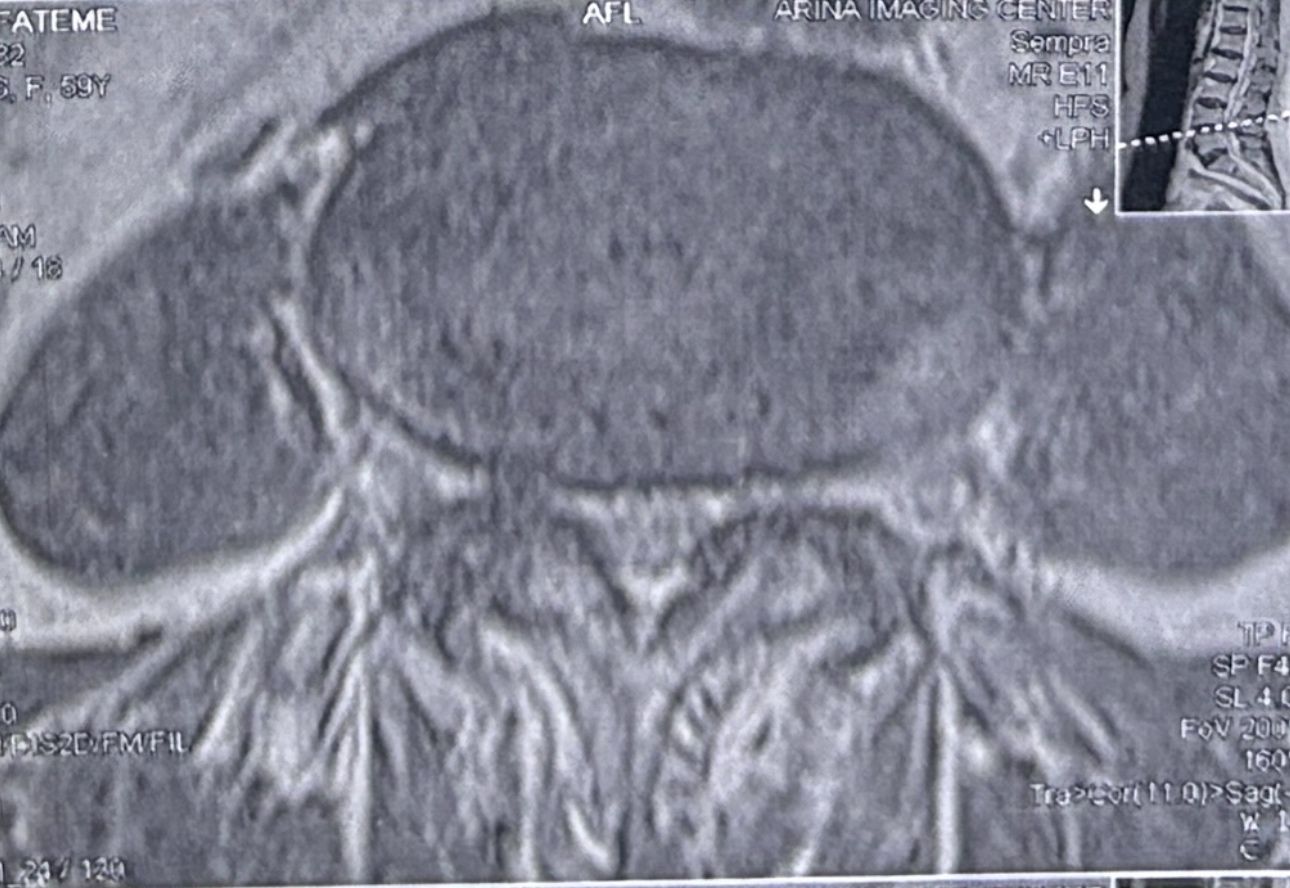

46 years old female patient presented to my clinic yesterday june 1/2025 with LBP and radicular L leg pain for several months which hasn’t responded to physio 2 neurosurgeons have visited her and didn’t suggest any surgery Neurological exam was unremarkable please see her mri/ emg/ncv and her huge tarlov cyst and possible L IVF L4-5 hyperbulge I ordered sacrum mri and ct scan and new emg/ncv and asked her with her sacral Ct scan and MRI first sees another two famous neurosurgeons and see if that large cyst is the reason for her pain if not i can work on her L4-S1 area Do you think her radicular pain can originate from her large cyst in sacrum? Do you consider surgery and removing her sacral cyst?